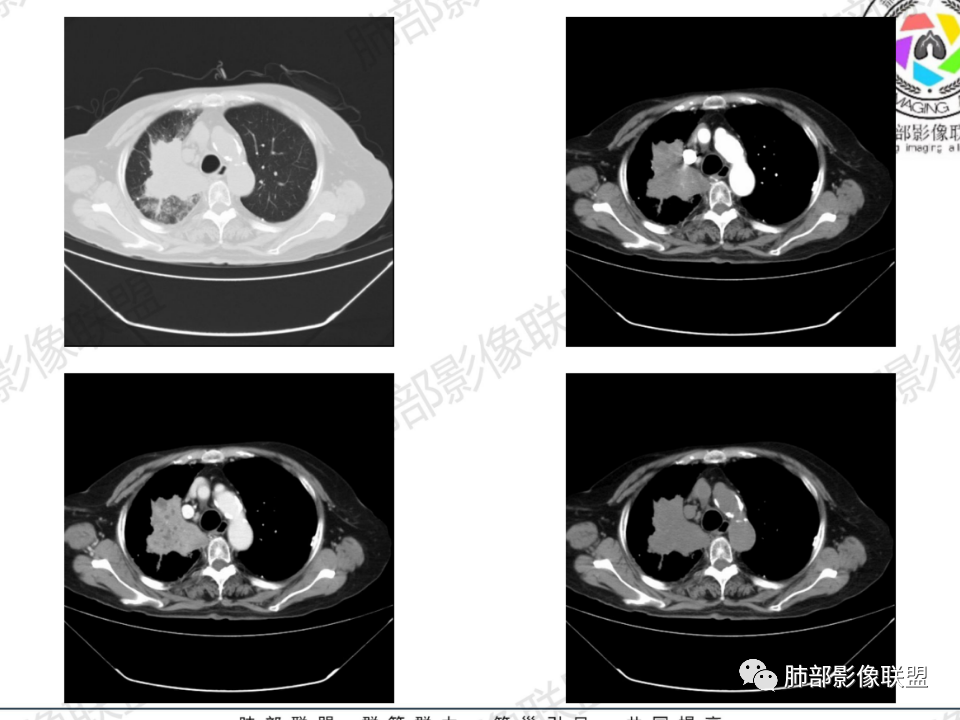

老年患者,病程中等,有咳嗽/喘息/低热症状,肿瘤标志物升高,感染标志物不高,右上肺新生物,中央型,边界清楚,有分叶,支气管截断,内有坏死,不均匀强化,考虑肺癌,鳞癌?

那个人:老年女性,亚急性病程,咳嗽发热。有垂体前叶功能减退,目前激素替代治疗,长期激素,量小,不知道累积量,没有目前激素水平指标。既往有淋巴结结核病史。肿瘤标记物Ca125升高。血沉升高,C反应蛋白轻度异常。影像,右肺上叶靠近肺门团块影,右肺门淋巴结钙化肿大,支气管狭窄,局部增厚,团块影外朝内改变,强化明显,血管破坏不明显,有粘液。和纵隔胸膜分界清楚,周围肺组织有斑片渗出影,右侧胸腔积液,考虑炎性?结核?支气管镜检查除外恶性飞鹰行动:老年患者,影像表现 右肺上叶占位性病变,边界清楚,有分叶征,内见细小钙化,右肺上叶支气管截断,增强病灶不均匀强化,病灶内有条状坏死区(扩张的支气管?),纵膈内未见增大淋巴结,考虑炎性病变,结核可能。一切∮随缘:右肺上叶实性肿块形态不规则,呈三角形,边缘分叶,边界伴有磨玻璃影,近段支气管未见明显显示,可能堵塞,病变平扫密度均匀,增强后可见低密度坏死无强化,周围略强化,右肺下叶散在结节。心包积液,及右侧胸腔积液,临床:有低热,低蛋白血症,肿瘤标记物高,考虑恶性:腺癌,神经内分泌癌(强化偏弱了),淋巴瘤,鉴别:结核红星:老年女性患者右肺上叶,肺门上区 分叶状肿块 ,右肺上叶支气管显示不清,增强扫描肿块,中等程度强化可见小斑片状坏死区,病灶内部可见斑点状钙化灶,病灶周围可见斑片状及小斑点状影,纵膈淋巴结增大,其他区域,胸膜下可见斑点状钙化。考虑肉芽肿性病变,结核的可能性大。老年患者最排除肿瘤性病变腺癌。土娃:右上肺不规则肿块影,边缘分叶,边界磨玻璃影欠清,病灶分叉状,内见点状钙化影及坏死灶,支气管堵塞,病灶增强强化不明显。考虑瘤样结核,鉴别淋巴瘤。张小兵:老年女性,亚急性病程,右肺上叶见不规则肿块,边缘平直凹陷为主,周围GGO边界不清,内见点状钙化及坏死灶,增强持续性渐进强化,右侧少量胸腔积液,双肺门及纵隔肿大淋巴结伴钙化,综合考虑慢性炎症。saf:老年患者,影像表现 右肺上叶占位性病变,边界清楚,有分叶征,增强病灶明显不均匀强化,纵膈内未见增大淋巴结,考虑炎性病变,结核可能。小兜:老年女性,咳嗽喘息一月,发热三天,肿瘤标志物升高,长期激素替代治疗。CT示右肺上叶近肺门不规则实变影,周围伴磨玻璃影,增强持续性渐进强化,内部血管破坏不厉害,内部可见多发条形低密度灶,右侧胸腔可见少量积液,双肺门及纵隔可见钙化淋巴结,考虑为炎性病变,结核可能玫:女,79咳嗽,喘息一月,发热三天入院,右肺上叶不规则形软组织密度肿块影,边界清晰,边缘见分叶及细短毛刺,病灶内见点状钙化影及稍低密度区,病灶边缘呈磨玻璃样改变,增强扫描,病灶呈不均匀性强化,考虑炎性病变,鉴别鳞癌。大雄:老年女性,既往诊断淋巴结结核,提示已治愈,近2年服用激素,诱导结核复燃→发热;纵隔肺门淋巴结肿大钙化,压迫支气管,右肺上中下叶支气管均狭窄→喘息咳嗽;尖段支气管受累闭塞→肺不张、支气管粘液栓;累及胸膜,结核性胸膜炎并胸水→右侧胸痛;实验室,血沉快,CA125高,低蛋白,符合;下一步,支气管镜尖段支气管刷检抗酸染色周太狼:老年女性,亚急性病程,肿瘤标志物升高。CT示右肺上叶尖段不规则肿块影,有分叶、收缩,周围伴磨玻璃影,增强渐进强化,内部可见多发条形低密度灶,右侧胸腔及心包少量积液,纵隔内淋巴结稍增大。倾向于恶性病变,肺癌伴阻塞性炎变可能。丽:老年女性,右肺上叶不规则软组织肿块,边缘清晰,内密度不均,可见点状钙化及粘液栓,周围可见片状高密度影,增强后均匀强化,内多发低密度,纵膈多发钙化淋巴结,考虑结核可能大,建议结合支气管镜检查除外肿瘤宇宙:右胸廓缩小,右肺上叶团块影及不张,平直边,周围磨玻璃影,纤细胸膜牵拉,上叶尖段支气管堵塞,明显延迟强化,可见支气管粘液栓,两肺门钙化淋巴结,右侧胸水,考性炎性肉芽肿,鉴别腺癌王秀仙:右肺上叶肺门区肿块,上叶支气管开口阻塞,形态不规则,密度不均,内可见支气管粘液栓及多发小灶性坏死,周围磨玻璃影边缘模糊,渐进强化,右侧胸腔积液、胸膜钙化,考虑炎性肉芽肿性病变,慢性炎症。鉴别鳞癌,结核。刘丹:老年女性,右肺上叶肿块伴钙化,右肺上叶支气管截断,增强后均匀强化,周边可见点片状模糊影,右侧胸腔积液,右肺门淋巴结增大,考虑占位并阻塞性炎症,肿瘤?结核?建议纤支镜检查。小飞:右肺上叶纵隔旁软组织肿块,边缘深分叶、长毛刺及毛刷样短毛刺,边缘磨玻璃影,磨玻璃边界模糊,支气管截断,平扫密度不均,可见点状钙化,增强不均匀明显强化,心影增大,心包积液,右侧胸腔积液,考虑恶性肿瘤,腺癌?秦化君:右肺上叶不规则分叶软组织密度肿块,边缘清晰,胸膜牵拉,周围花花草草,上叶尖段支气管阻塞,内可见点状钙化,增强后密度不均可见支气管粘液栓及坏死区,内见血管分枝。中间段及中叶,下叶支气管狭窄,壁见钙化。右肺门淋巴结肿大,右侧胸腔积液,心包粘连肥厚。考虑1右上肺恶性病变,鳞癌?2右肺多叶段支气管狭窄,考虑支气管内膜结核?3胸腔积液及肺门淋巴结肿大,转移?风儿:老年女性,右肺上叶肿块,形态不规则,外围大内带小,边缘分叶膨隆平直及毛糙,密度不均,内见支气管粘液栓及多发小灶性坏死,坏死边缘清晰 ,渐进强化,上叶尖段支气管阻塞,叶支气管壁有局限性增厚,邻近胸膜腔微积液;纵隔及双肺门淋巴结肿大,部分钙化,右侧胸腔积液、心包积液、胸膜钙化,考虑炎性,肉芽肿性结核可能性大。鉴别鳞癌,女性及血供均不支持;腺癌,坏死边界太清晰。流心明智:老年女性,79岁,咳嗽、气短1月,发热3天。胸CT:右肺上叶见不规则肿块,边缘有膨隆、有平直凹陷,周围GGO边界不清,病灶内见点状钙化、粘液栓,尖段支气管未见,增强持续性渐进强化,右侧少量胸腔积液,双肺门及纵隔肿大淋巴结伴钙化,肺动脉增粗。考虑:右上叶尖段堵塞并慢性炎症,支气管TB并结石?鉴别Ca

右肺体积小,提示既往结核

支气管影

前,后段都在,没有堵塞

支气管壁增厚,周围磨玻璃边界不清,提示炎症。胸膜下钙化符合结核

近期发热符合感染

这个层面往上应该是尖段,显示不清

背段支气管周围增厚伴钙化,符合结核改变

胸腔积液并胸膜钙化,符合结核;

结核是肯定有。现在最大问题是尖段

近端显示不清,但是远端是粘液栓,可以认为是还行的

如果是近端鳞癌,远端应该会堵塞,不会整个肿块里面还有较为通畅的支气管

这个区域我们看到密度与周围一致,并不是肺癌伴周围不张的感觉,所以鳞癌暂时是不支持的

临床信息:老年女性,亚急性病程,咳嗽发热。有激素使用史。既往有淋巴结结核病史。肿瘤标记物Ca125升高。血沉升高,C反应蛋白轻度异常。 影像所见:右侧胸廓相对狭小,右肺上叶不规则团块影贴附纵隔旁,轻度分叶,整体密度较均匀,偶见钙点。

相应上叶尖端及前段支气管开口未能追踪(阻塞),开口处见钙化。病灶渐进性强化,并衬托出较完整尖段及前段含液支气管影。支气管开口区域未见异常高密度强化(如类癌等)及相对乏血供区(如鳞癌)。病灶区未见液化坏死。右上纵隔及胸廓入口区未见病灶胸膜外突破(栽赃)。

右肺上叶后段等区域散在片状影,边界不清(提示渗出性病灶)。

纵隔及双肺门见钙化淋巴结。心包积液,右侧胸腔积液(提示存在活动新病灶)。双侧胸膜下见多发斑点状钙化,胸廓变形(提示存在结核基础病变可能)。 诊断意见:综上,右肺上叶块状影更符合继发性肺结核。 最后小结:既往诊断淋巴结结核,提示已治愈。近2年服用激素,可疑诱导结核复燃,也可引起发热。纵隔肺门淋巴结肿大钙化,压迫支气管,右肺上中下叶支气管均狭窄,所以引起喘息咳嗽。尖段支气管受累闭塞,导致肺不张、支气管粘液栓,出现条状无强化区。病变累及胸膜,导致结核性胸膜炎并胸水,引起右侧胸痛。实验室检查血沉快,CA125高,低蛋白,均符合结核。下一步,建议支气管镜尖段支气管刷检并抗酸染色。(本段摘自於雄老师精彩发言)